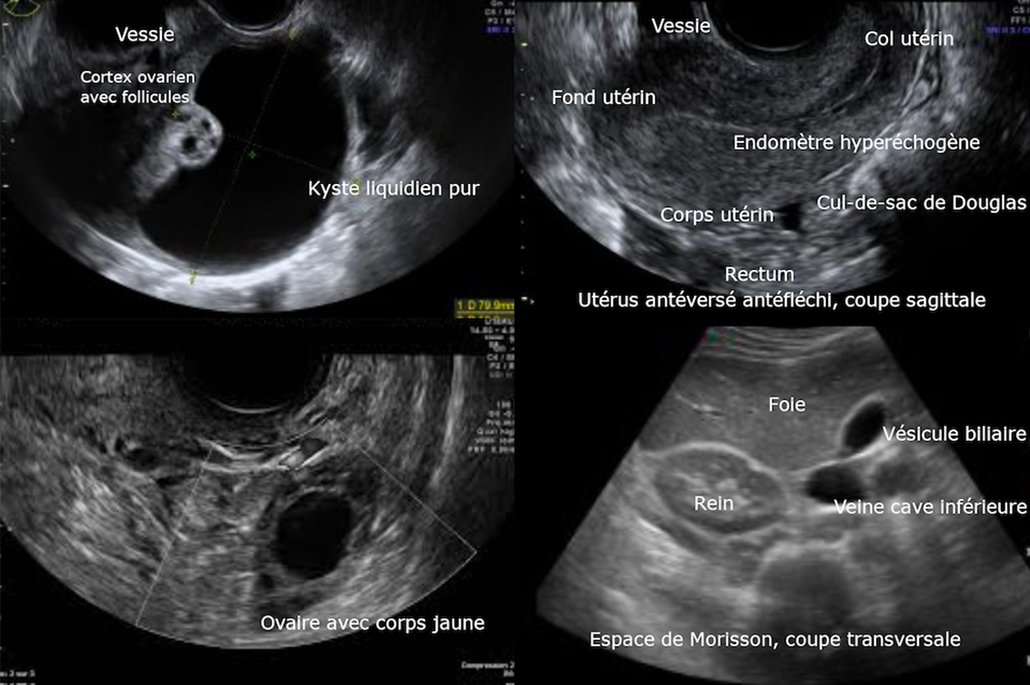

Une échographie pelvienne abdominale puis endovaginale est réalisée (figure 1). Elle montre :

– ovaire gauche augmenté de volume (75 × 55 mm), contenant un kyste uniloculaire finement échogène de 60 mm, à paroi fine, sans végétation ;

– ovaire droit sans particularité ;

– lame d’épanchement dans le cul-de-sac de Douglas.

Figure 1 (Rodolphe Matias de Sousa, La Revue du Praticien)

La triade douleur pelvienne aiguë brutale, nausées, vomissements est évocatrice de torsion d’annexe chez la femme en âge de procréer. La figure 2 illustre les différents critères échographiques d’une torsion annexielle (ovaire augmenté de volume [> 4 cm], souvent porteur d’un ou plusieurs kystes, hyperéchogène compte tenu de l’œdème, avec parfois l’absence de vascularisation au Doppler, et un ovaire controlatéral habituellement d’aspect normal).

Figure 2 (Rodolphe Matias de Sousa, La Revue du Praticien)